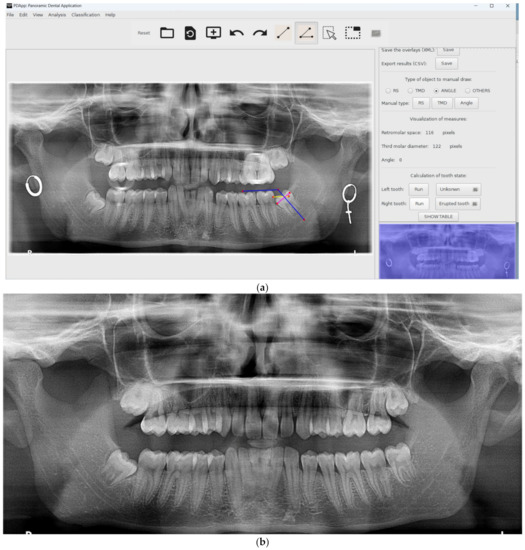

Figure 4. Visual example of a third molar erupted, predicted correctly by PDApp. The pink line represents third molar diameter, the yellow line represents retromolar space, and blue lines represent the angle of eruption.

The software is reliable and precise because it allows reviewing the classification of mandibular third molars. Figure 5, image (a) shows a case of a third molar that is classified as erupted by PDApp and image (b) a posterior panoramic radiograph images confirms the PDApp results. It is also easy to use and install. Another advantage that the program offers compared with manual quantification is the possibility of sharing the images and results among other experts to evaluate each case, reducing the variability among experts.

Figure 5. Visual example of correct prediction The pink line represents third molar diameter, the yellow line represents retromolar space, and blue lines represent the angle of eruption: image (a) shows partial retained third molar is classified as erupted tooth by the software; image (b) confirms the eruption of third molar (panoramic one year later). The screenshots have been taken using the windows version of PDApp.